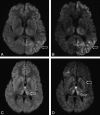

Background and purpose: DWI using a standard b-value of 1000 s/mm(2) has emerged as the most sensitive sequence for the diagnosis of CJD. The purpose of this study was to investigate whether DWI at a high b-value (b = 3000 s/mm(2)) and ADC measurements in the basal nuclei improve the diagnosis of vCJD and sCJD compared with visual assessment of DWI at a standard b-value (b = 1000 s/mm(2)).

Materials and methods: Eight patients with vCJD, 9 patients with sCJD, and 5 healthy volunteers underwent DWI at b = 1000 s/mm(2), and 5 vCJD patients, 4 sCJD patients, and 1 growth hormone-related CJD patient underwent DWI at b = 3000 s/mm(2). Two consultant neuroradiologists performed a visual comparison of the b = 1000 and b = 3000 images. Mean MR SI and ADC values were determined for C, P, and DM thalamus ROIs bilaterally at each b-value. SI ratios for each ROI relative to white matter were calculated.

Results: In 9 out of 10 patients, the higher b-value images were more sensitive to SI change, particularly in cortex and thalamus, with higher SI ratios at b = 3000 in the DM thalamus. For sCJD at b = 1000, we found significantly lower ADC values in the C and P compared with controls (mean C ADC = 587.3 +/- 84.7 mm(2)/s in sCJD patients versus 722.7 +/- 16.6 mm(2)/s in controls; P = .007), and at b = 3000, the differences were more pronounced. In comparison, in vCJD at b = 1000, ADC values were elevated in the Pu (mean Pu ADC = 837.6 +/- 33.0 mm/s(2) in vCJD patients versus 748.0 +/- 17.3 mm/s(2) in controls; P < .001) but failed to reach significance at b = 3000.

Conclusions: Our results demonstrate that b = 3000 DWI, being more sensitive to slowly diffusing tissue water, is more sensitive to pathology in sCJD than is conventional DWI. High-b-value DWI increases confidence in the radiologic diagnosis of human prion disease.